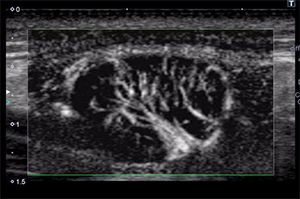

SMIを用いた診断画像

悪性リンパ腫(モノクロ表示モード) |